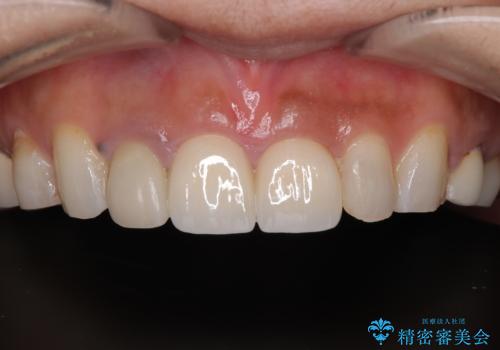

オールセラミッククラウンは透明感が高く、自然な歯の色調に調整でき、歯と歯ぐきの境目もとても自然な仕上がりとなりました。

患者様からも「以前よりも自然で、笑った時の印象がとても良くなった」と、大変満足のお声をいただきました。